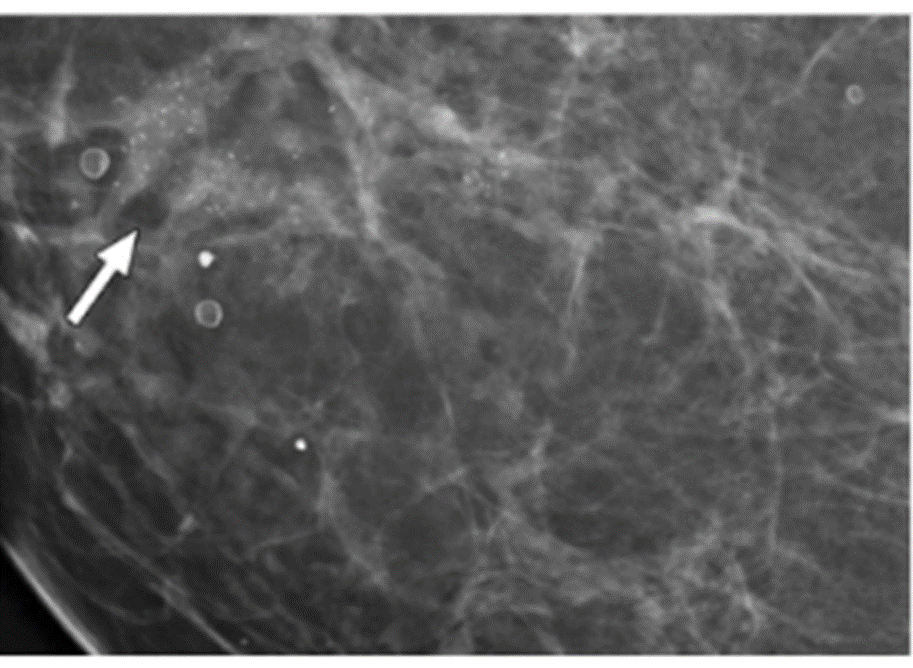

Đây là phương pháp chụp X-quang vú đặc biệt, đóng vai trò quan trọng trong tầm soát ung thư vú. Đây là thủ thuật sử dụng tia X cường độ thấp chiếu vào các mô tuyến vú để thu lại hình ảnh tại tuyến vú. Qua hình ảnh thu được từ chụp X-quang vú, bác sĩ có thể phát hiện các bất thường và khối u ở giai đoạn sớm ngay cả khi bệnh nhân chưa phát hiện, sờ thấy.

Kỹ thuật chụp Mammography có những ưu điểm vượt trội như thời gian thực hiện nhanh, không xâm lấn, kết quả chính xác, chi phí hợp lý,... Nhiều nghiên cứu cho thấy chụp Mammography giúp giảm tỷ lệ tử vong của ung thư vú khoảng 30%. Vì vậy, các chuyên gia ung bướu ưu tiên chỉ định kỹ thuật chẩn đoán hình ảnh này. Những phụ nữ trên 40 tuổi nên chụp Mamo vú 1 - 2 lần/năm.

Khối mờ có nhiều nốt vi vôi hoá không đồng nhất, gián đoạn: nghi ngờ ung thư vú

Về ý nghĩa tầm soát và chẩn đoán bệnh, chụp X-quang vú mang lại những giá trị cụ thể như:

• Phát hiện tổn thương bất thường ở vú, hố nách 2 bên;

• Phát hiện các dấu hiệu vi vôi hóa mà siêu âm không phát hiện được - một trong những dấu hiệu ác tính của bệnh lý tuyến vú;

• Chẩn đoán sớm ung thư vú, kể cả với những khối u không sờ thấy được bằng cách thăm khám, những tổn thương kín đáo, những tổn thương trong lòng ống sữa, các tổn thương vôi hóa rất nhỏ với độ nhạy là trên 90%;